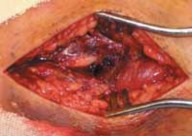

--- TECH FIG 2 • A. Cleaning the fracture site with a small curette. B An example of clamp placement across the fibular fracture site. Care is taken not to comminute the fracture spike. C. Lag screw placement, overdrilled with a 3.5-mm bit proximally. D. This is followed by drilling of the far cortex with a 2.5-mm drill. E. A neutralization plate is applied to the lateral surface of the fibula. F. Example of distal screw pen- G etration to be avoided. G. Wound closure. ANTEROMEDIAL APPROACH TO THE MEDIAL MALLEOLUS Exposure 1. The medial malleolus is approached via a gently curved anteromedial incision (

TECH FIG 3A

).

1. An incision is made parallel to the saphenous vein that is either concave anterior or concave posterior to allow visualization of the anteromedial joint.

TECHNIQUES A A

---

B

TECH FIG 3 • A. For a medial-side injury, the skin incision is curved about the medial malleolus. B. Fracture site is exposed and cleaned of hematoma and the talar dome is inspected for signs of chondral injury.

TECH FIG 4 • A. Reduction is achieved with a pointed reduction clamp. B. Guidewires for cannulated screws are placed across the fracture. 1. After dissection of the skin, the subcutaneous tissues should be carefully dissected to prevent injury to the saphenous vein and nerve.

2. With the dissection carried down sharply to the bone, the periosteum is elevated for 1 mm proximally and distally.

3. The fracture should be booked open to allow visual inspection of the talar dome for chondral injury.

4. The joint and medial gutter should be irrigated through the fracture for any loose hematoma or debris that may impede reduction (

TECH FIG 3B